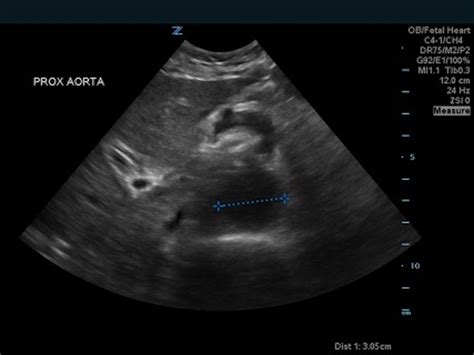

Diagnosing an Iliac Artery Aneurysm typically involves a combination of medical history, physical examination, and imaging tests. The diagnostic process may include:

• Ultrasound: This non-invasive test uses sound waves to create images of the iliac arteries and detect any abnormalities.